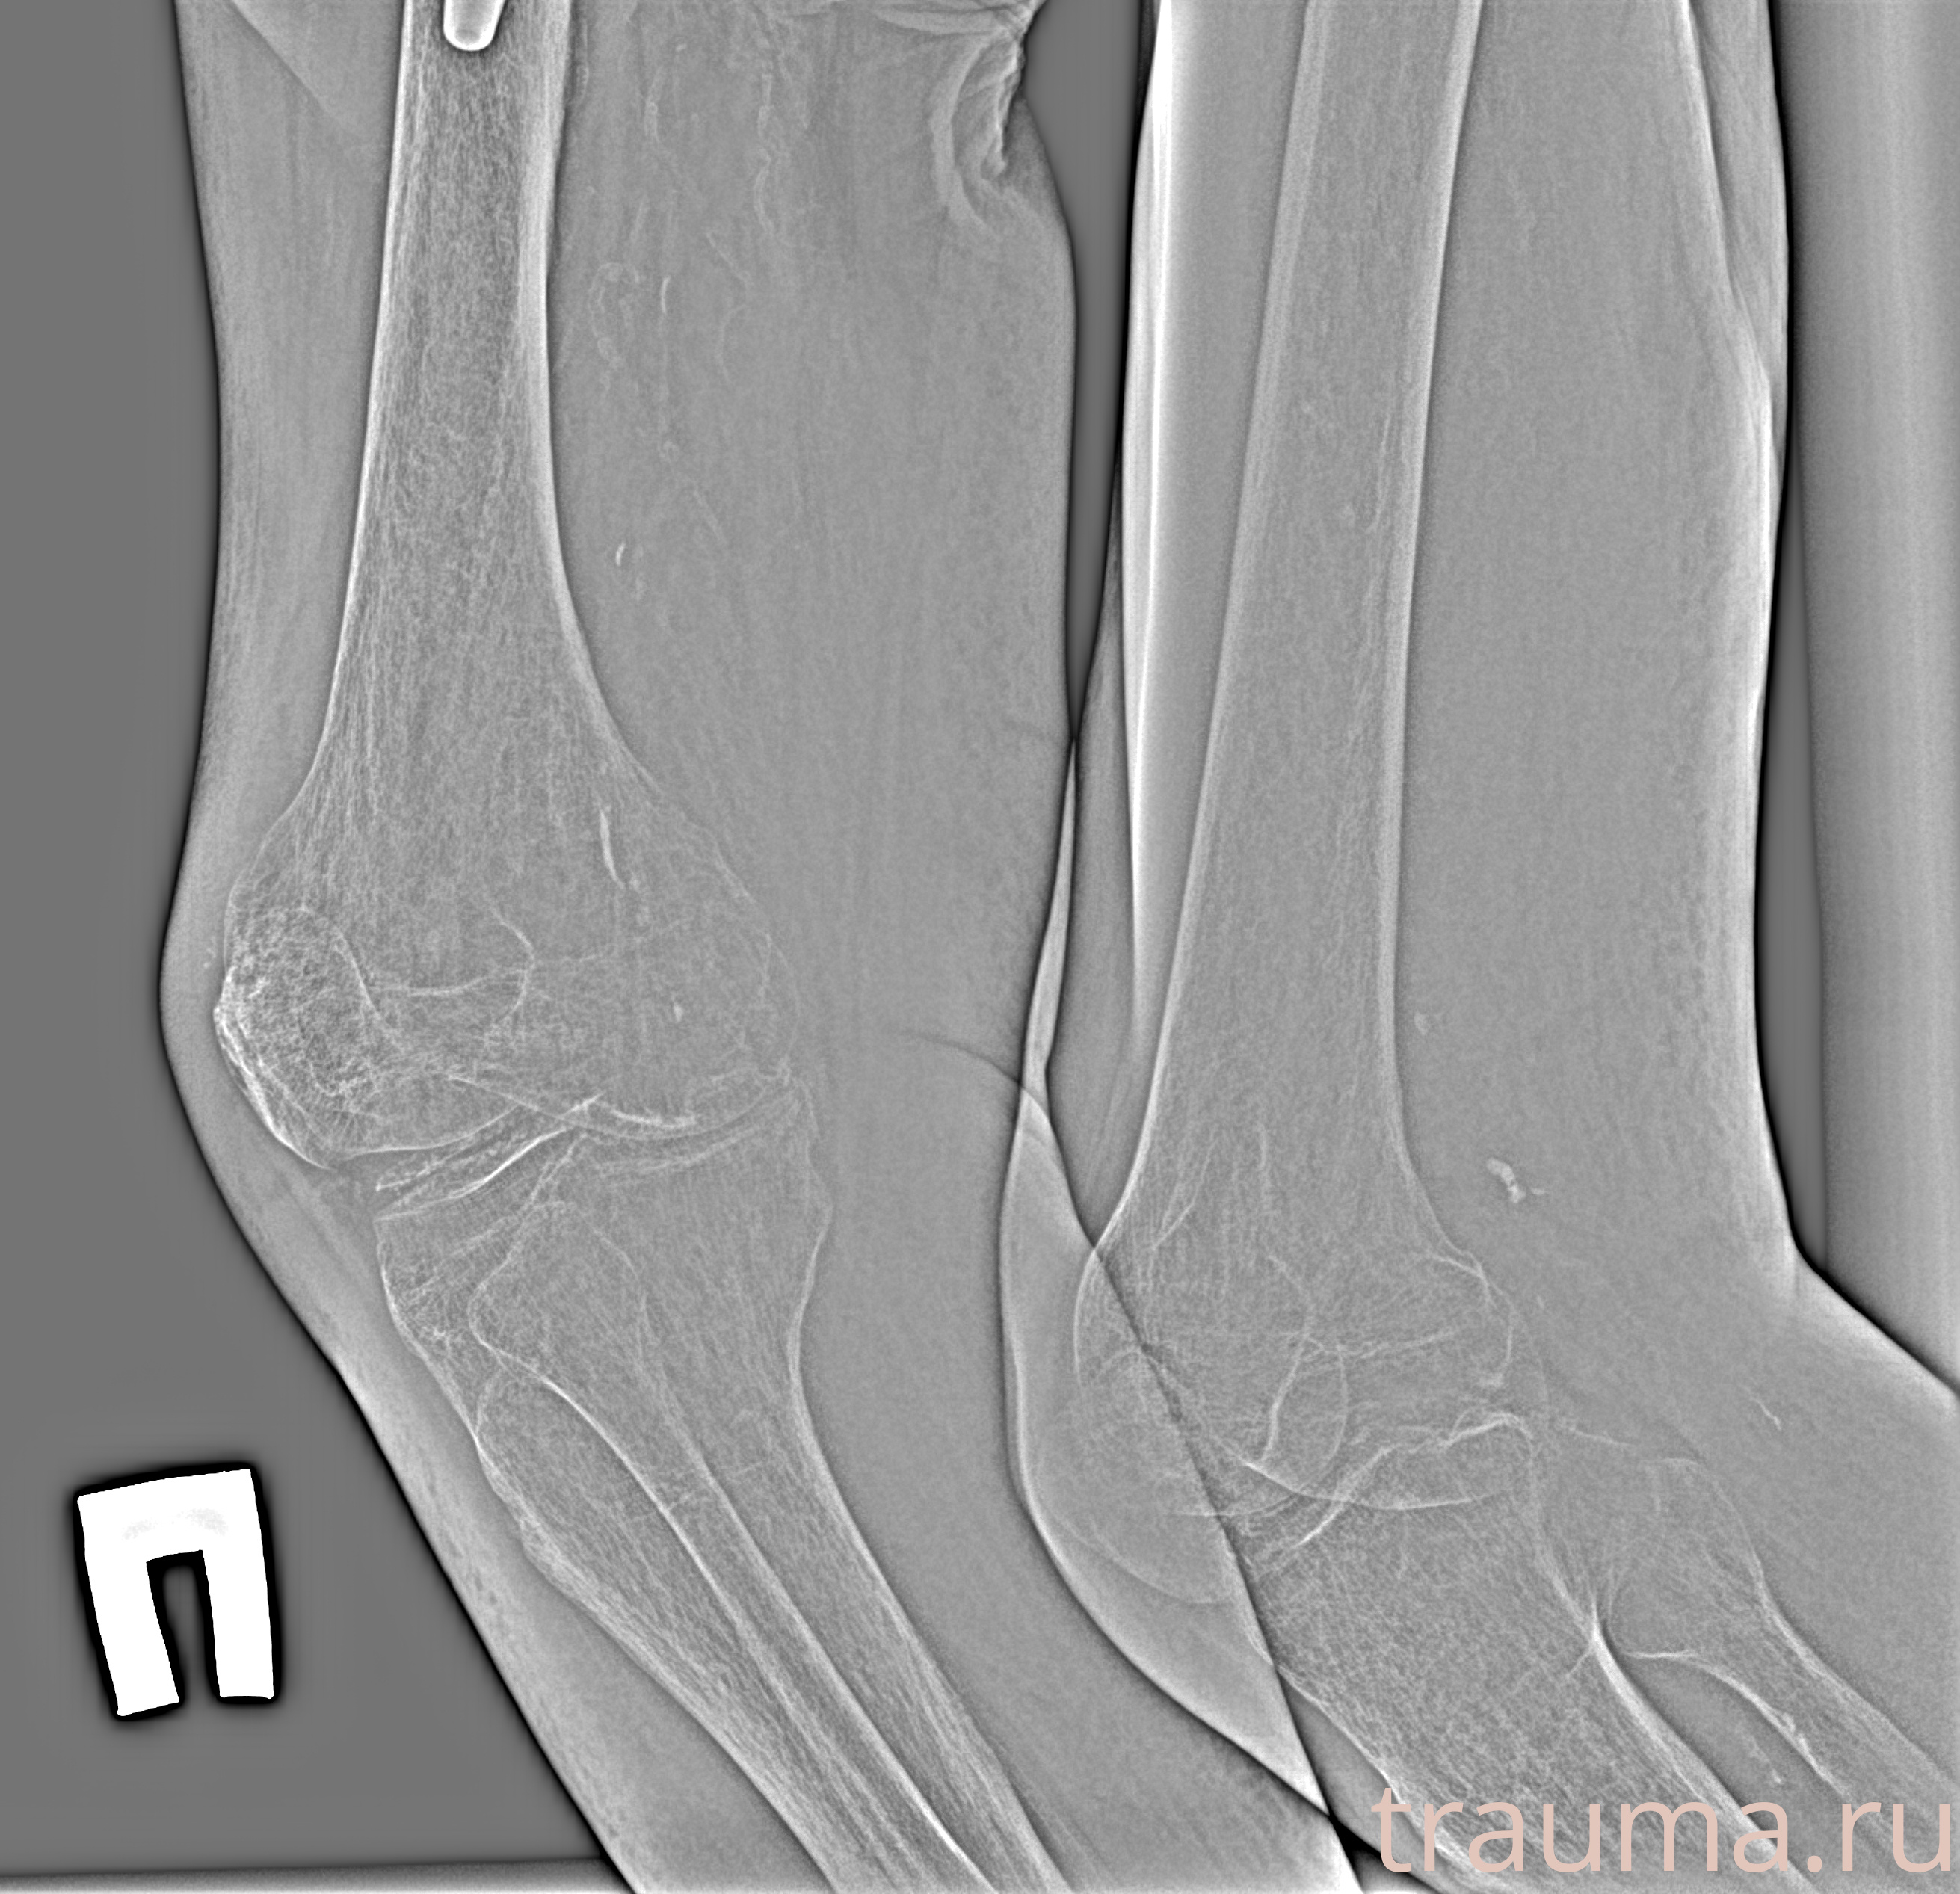

Рентген на дому: по вашему адресу приезжает врач-рентгенолог, травматолог-ортопед с мобильным рентгеновским аппаратом, проводит диагностику травмы или заболевания, делает необходимые рентгенограммы, дает рекомендации по дальнейшему лечению. Получить качественные снимки в домашних условиях возможно благодаря уникальной методике, разработанной МосРентген Центром для института  Склифосовского